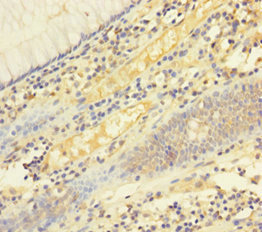

Immunohistochemistry of paraffin-embedded human liver cancer using CSB-PA008434LA01HU at dilution of 1:100

Immunohistochemistry of paraffin-embedded human colon cancer using CSB-PA008434LA01HU at dilution of 1:100